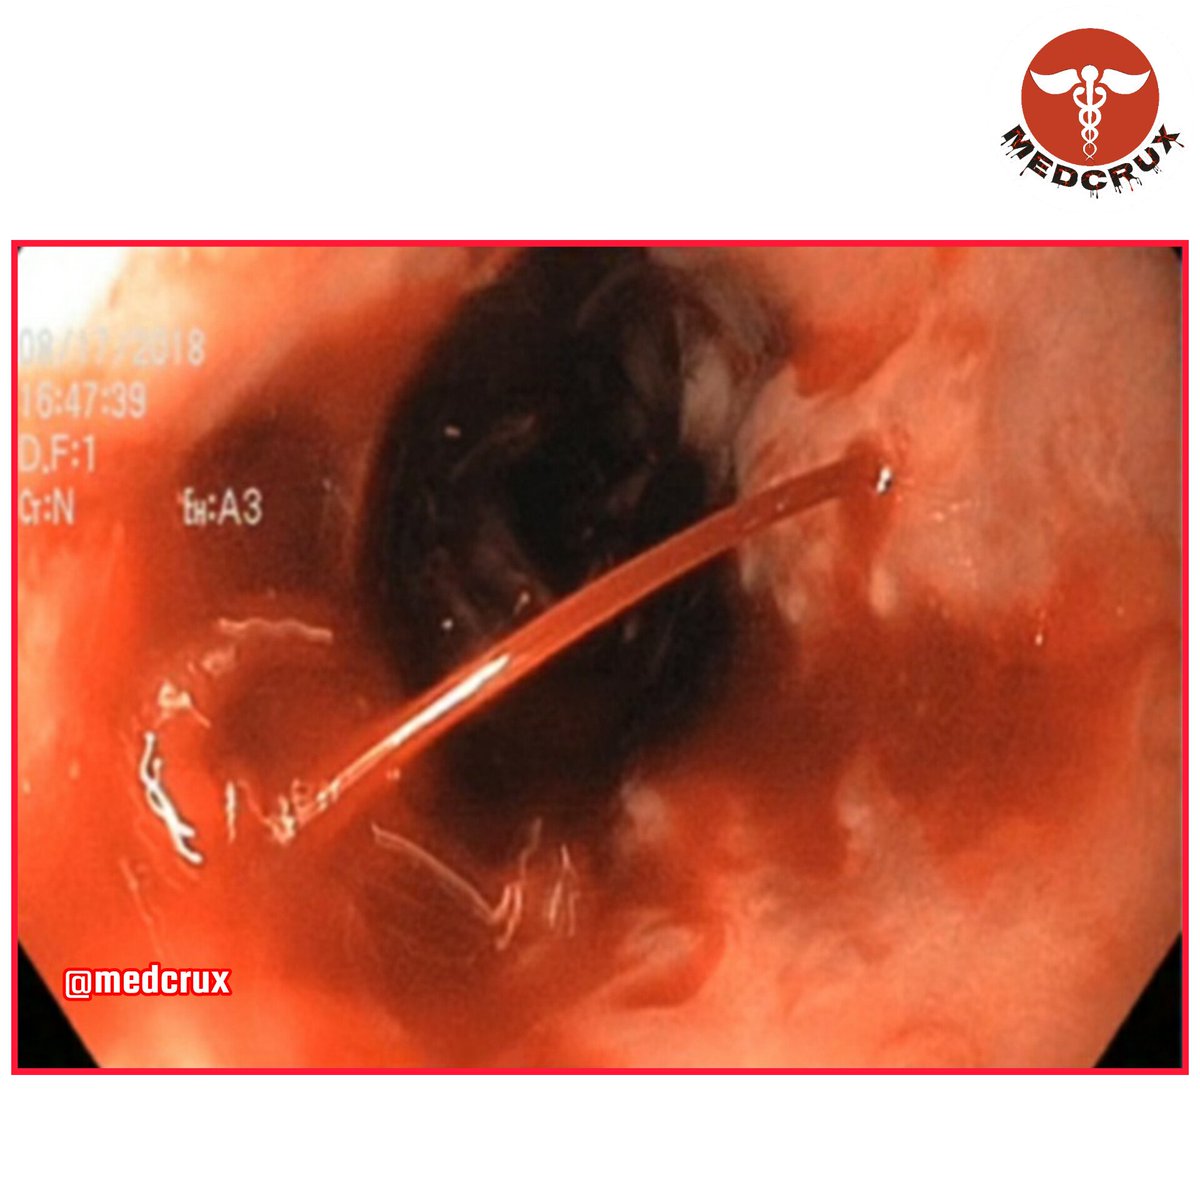

@medcrux

🙍‍♂️ A 60 YO man with hematemesis, melena, ascites & splenomegaly due to portal hypertension. Endoscopy shows dilated veins in lower esophagus. Diagnosis❓ A) Peptic ulcer B) Mallory-Weiss tear C) Esophageal varices D) Gastric carcinoma 💬 Comment your answer below 👇